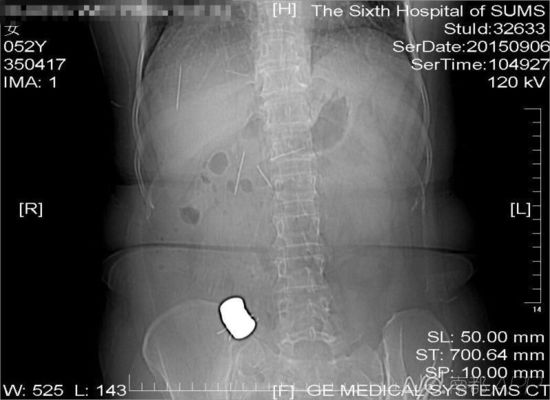

CT檢查結(jié)果中顯示,老人腹中有多個金屬異物和散落的繡花針

進(jìn)行的CT檢查結(jié)果顯示,黃姨腹中有多個金屬異物和散落的繡花針。主管醫(yī)生黃俊博士介紹,這些針分別位于黃姨小腸內(nèi),部分已經(jīng)穿出小腸散播于腹腔內(nèi),還有部分金屬異物,最大的一塊上附著了數(shù)根斷針,有一根插進(jìn)了胰腺,剩下的一根在脊柱附近,每枚約長4厘米。